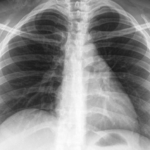

【画像】 お医者さんに見せられたモノ 言われたこと